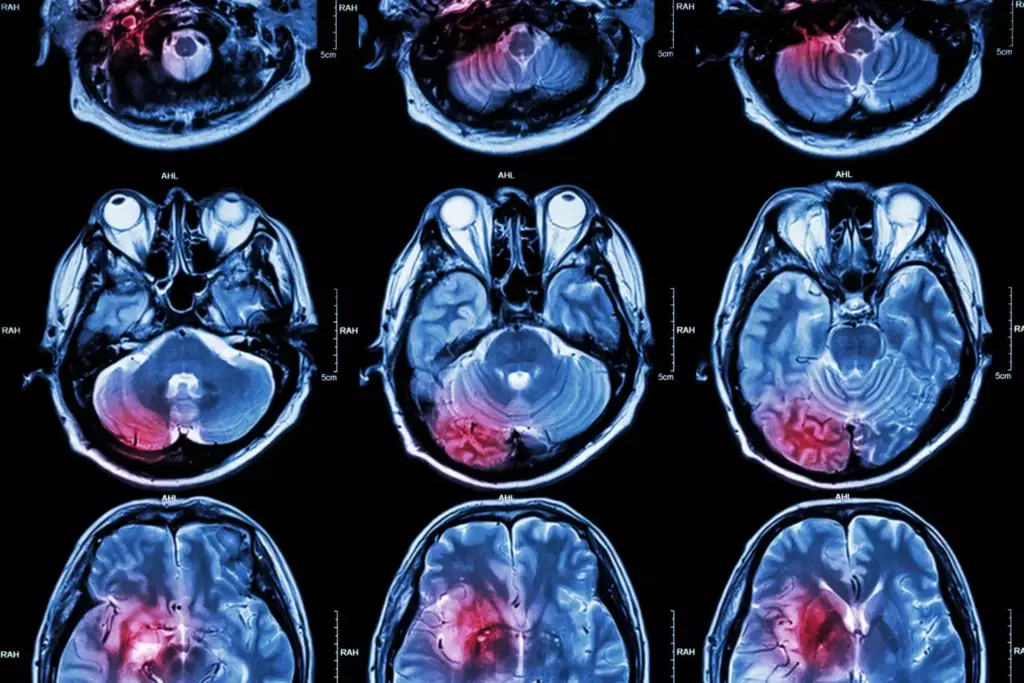

Brain cancer and its symptoms are closely linked to the type and growth pattern of the tumor. Brain tumors can significantly impact brain function. This leads to a variety of symptoms, including headaches. Understanding these tumors is key to grasping how they affect the brain and cause these symptoms.

Brain tumors can be primary (originating in the brain) or secondary (metastasizing from other parts of the body). Primary brain tumors are classified into different types based on the cell of origin. These include gliomas, meningiomas, and medulloblastomas. The growth patterns of these tumors vary; some grow slowly, while others are more aggressive.

Brain tumors cause symptoms by compressing or infiltrating surrounding brain tissue. This disrupts normal brain function. Headaches occur due to increased intracranial pressure or direct irritation of pain-sensitive structures. Other symptoms can include neurological deficits, seizures, and cognitive changes, depending on the tumor’s location and size.